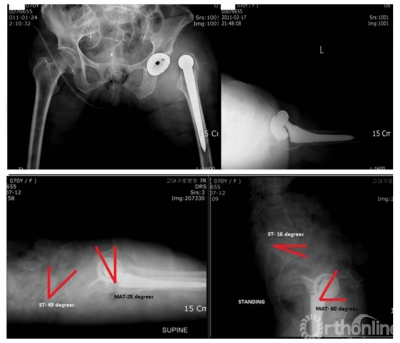

骨盆活动度与体位变化对THA的影响

上述介绍了从仰卧位到站立位的骨盆矢状面变化,那么不同体位对THA术后人工关节有何影响?既往系统综述显示,从769项报道中筛选12个RCT研究中,过高的骨盆活动度(站立位和坐位)骨盆前倾角变化较大,增加了假体撞击和脱位的风险。

图4 站立位到坐位髋臼角度的变化

图5 1例髋关节脱位患者髋臼角度的变化

坐位时髋臼前倾角变大,可以影响稳定性、增加边缘磨损、甚至脱位。对于骨盆活动度大患者,髋臼外展角>50°, 前倾角>25°,脱位的危险也明显增大。既往研究显示,从站立位到坐位,髋臼前倾增加7.1°,骨盆后倾增加14.5°;在矢状面上,坐位时骨盆后倾增加30°,髋臼前倾增加30.2°。